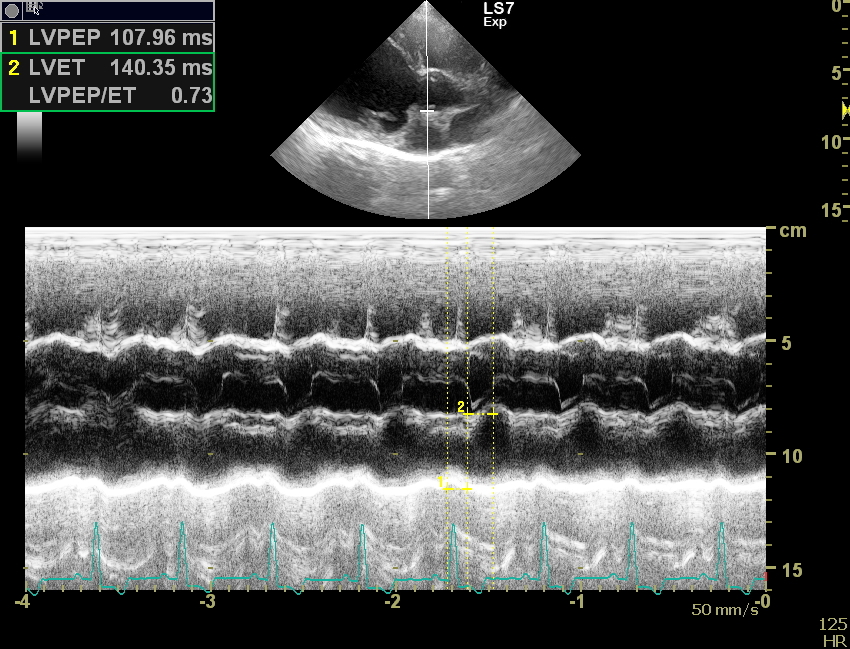

Weitergehend haben wir dann eine Herzultraschalluntersuchung durchgeführt um weitere Informationen über die zugrundeliegende Erkrankung zu bekommen. Auch in der Echokardiografie stellte sich das Herz deutlich zu groß da. Die linke Hauptkammer und der linke Vorhof sind massiv volumenüberladen, also mit zu viel Blut gefüllt. Durch die starke Blutfülle im Herzen hat sich auch der Klappenapparat der Mitralklappe aufgedehnt, sodass dieses Rückschlagsventil zwischen der linken Kammer und dem linken Vorhof nicht mehr richtig abdichtet. Resultat ist eine Mitralklappeninsuffizienz, die bei jedem Herzschlag etwas Blut in den linken Vorhof zurückfließen lässt. Der linke Vorhof wird, wie hier bei Faust sehr groß und das Blut staut in den Lungenkreislauf zurück, es entsteht ein Lungenödem. Vereinfacht gesagt Faust hat „Wasser auf der Lunge“, eine weitere wichtige Ursache für Husten bei unseren herzkranken Hunden. Die Herzmuskulatur bei Faust ist eher dünn und die Pumpkraft (Kontraktilität) der Herzmuskulatur ist sehr schwach.

Bei der Kontrolluntersuchung am 5. März mussten wir leider eine weitere Verschlechterung der gemessenen Werte feststellen. Faust hatte einige Tage zuvor wieder zu husten begonnen, das Blutvolumen im linken Herzen hatte noch einmal zugenommen, lediglich die Pumpkraft des Herzens war etwas besser als bei der Erstuntersuchung. Wir haben die Dosierungen der Herzmedikamente noch einmal angepasst und hoffen, dass es unserem Patienten nun noch lange gut geht.